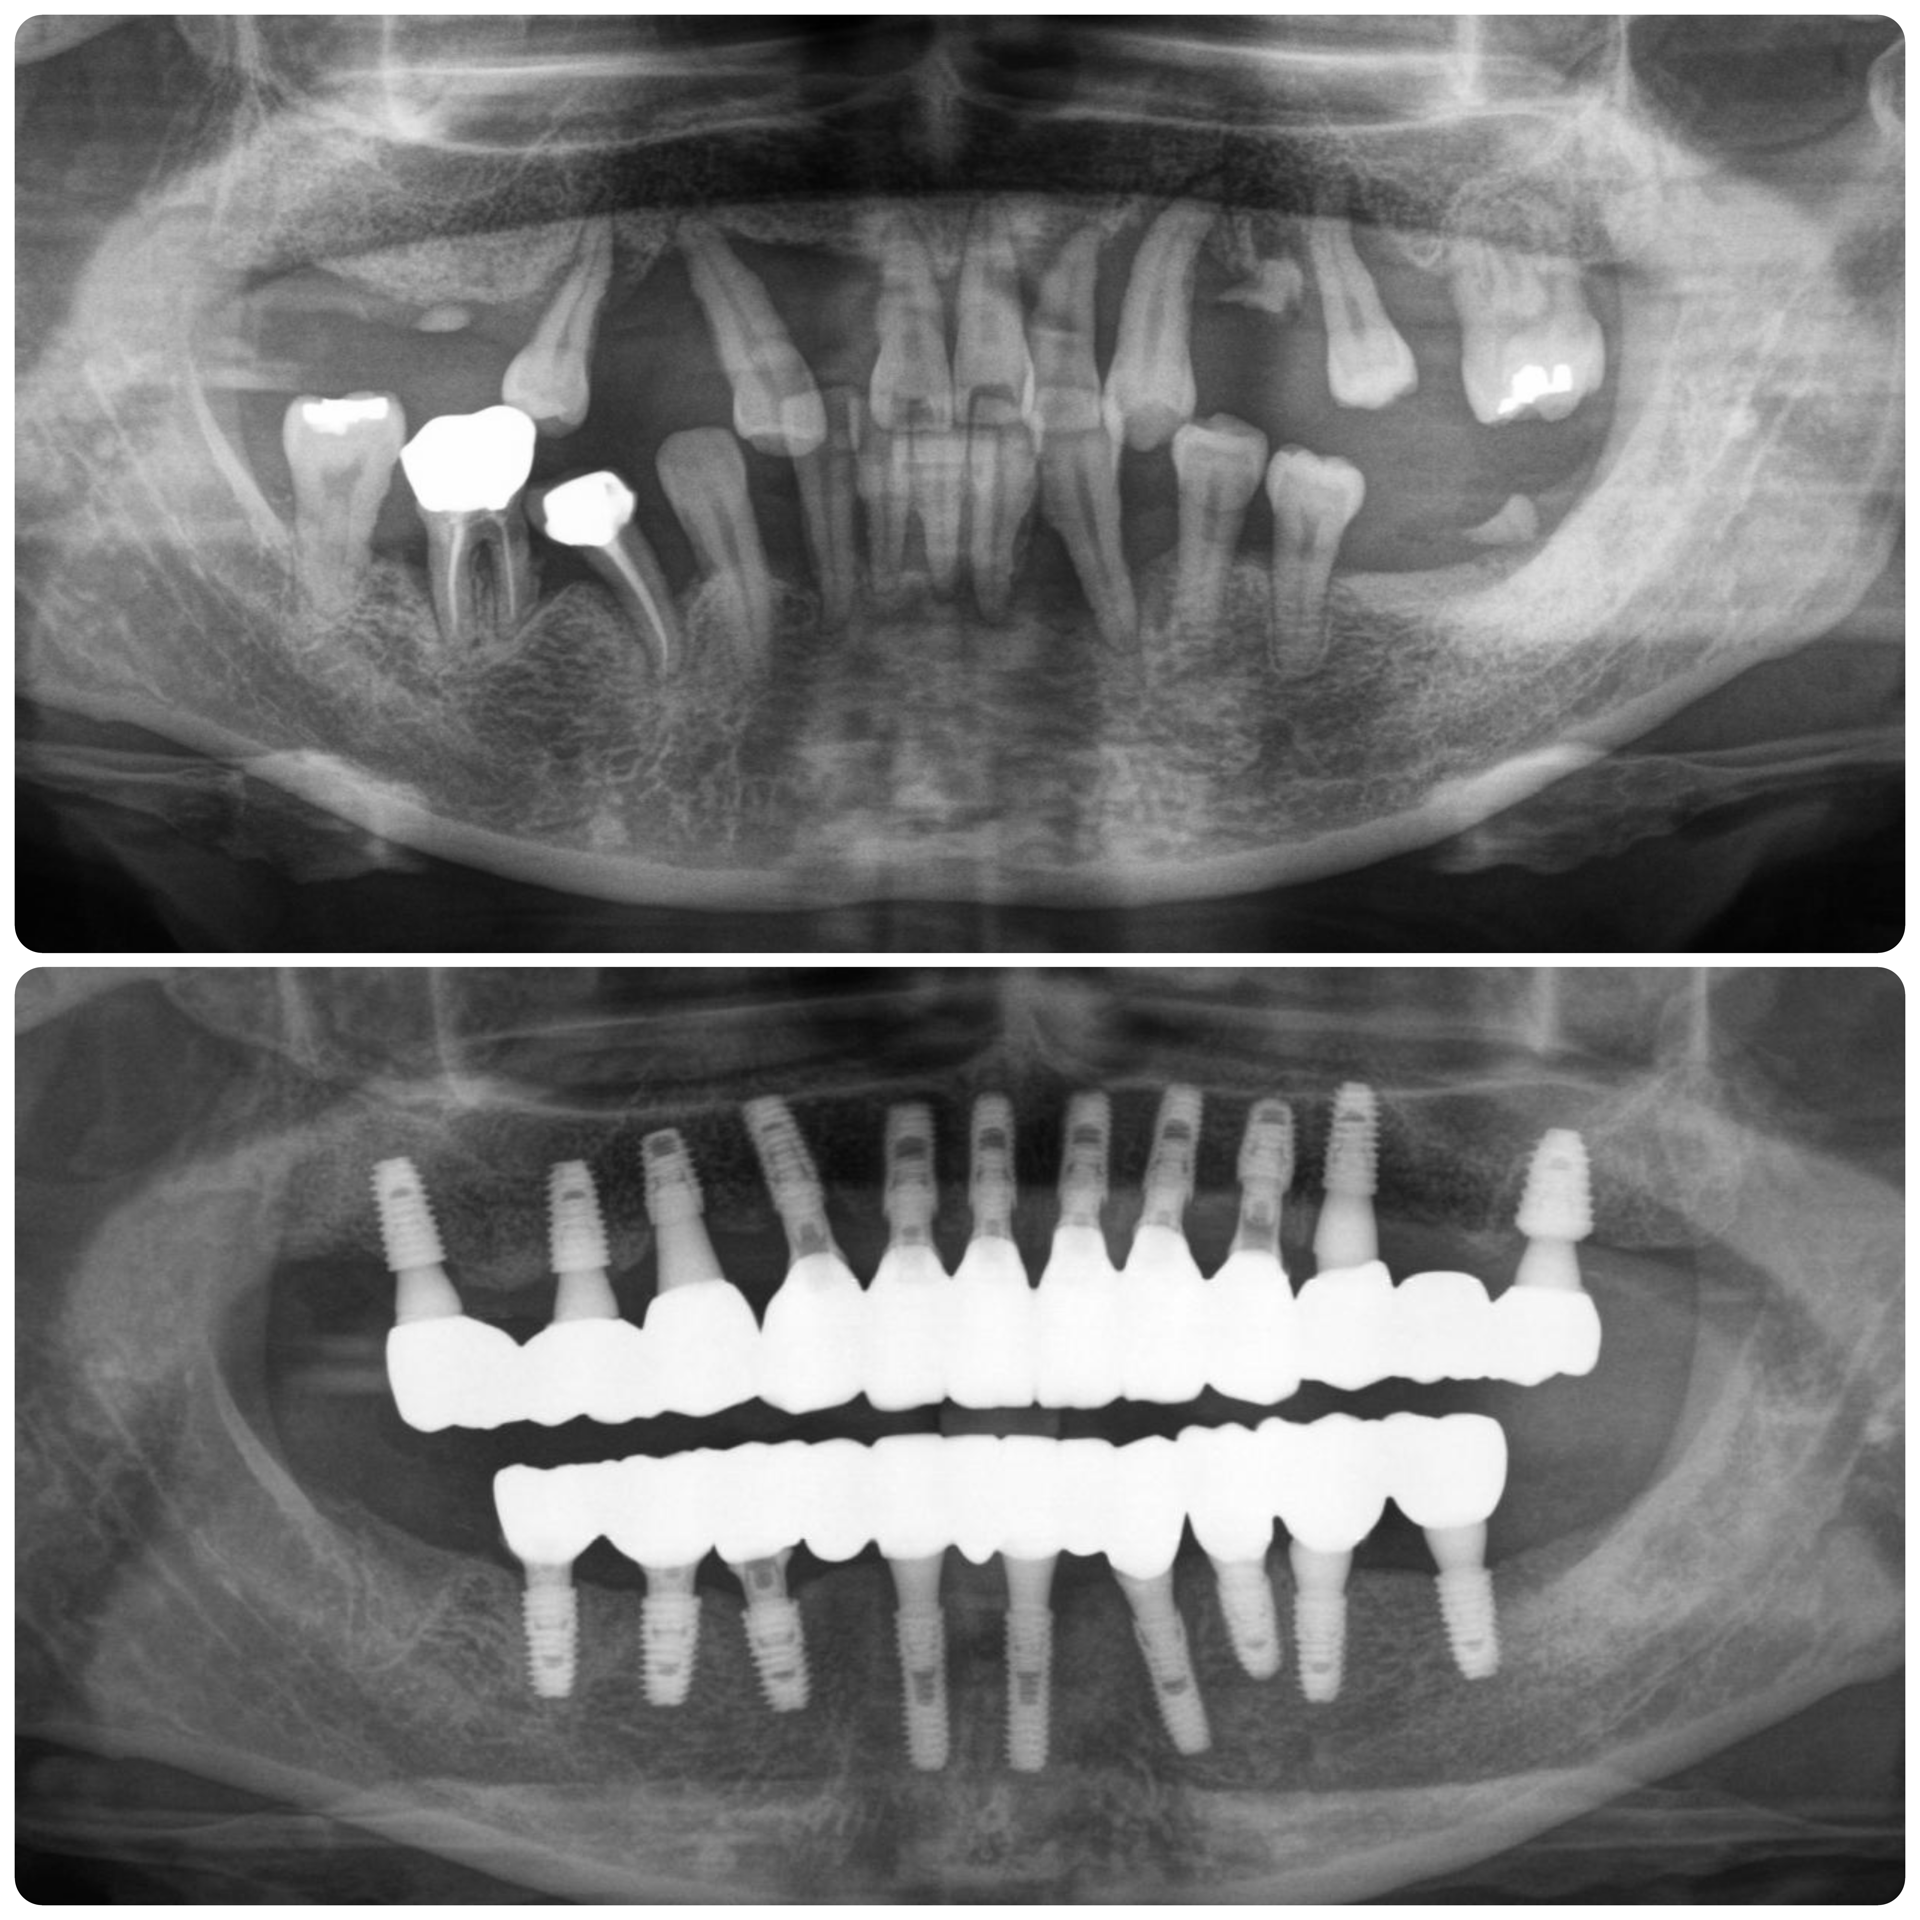

앞니임플란트 잘하는 노하우

1) 가능한 빨리 치료합니다.

2) 필요하다면 뼈이식을 해서 정확한 위치에 임플란트를 심습니다.

3) 앞니 디자인을 잘 해야 합니다.

4) 치아색 기둥을 이용하고 투명감있는 재료로 보철을 해야 합니다.

5) 내부결합형 locking형태의 임플란트를 이용합니다.

4. 앞니에 좋은 임플란트 디자인은?

그렇다면 다양한 임플란트 중에 어떤 것을 선택하는 것이 더 예쁠까요?

초창기에 개발되었던 외부결합형 임플란트보다는

내부결합형의 locking형태가 보다 안정적인 앞니의 잇몸라인을 보장한다고 말할 수 있습니다.

잇몸의 양의 더 풍부하고 또한 뼈의 소실이 거의 없어

장기적으로 안정적인 모양을 유지할 수 있다는 장점이 있습니다.